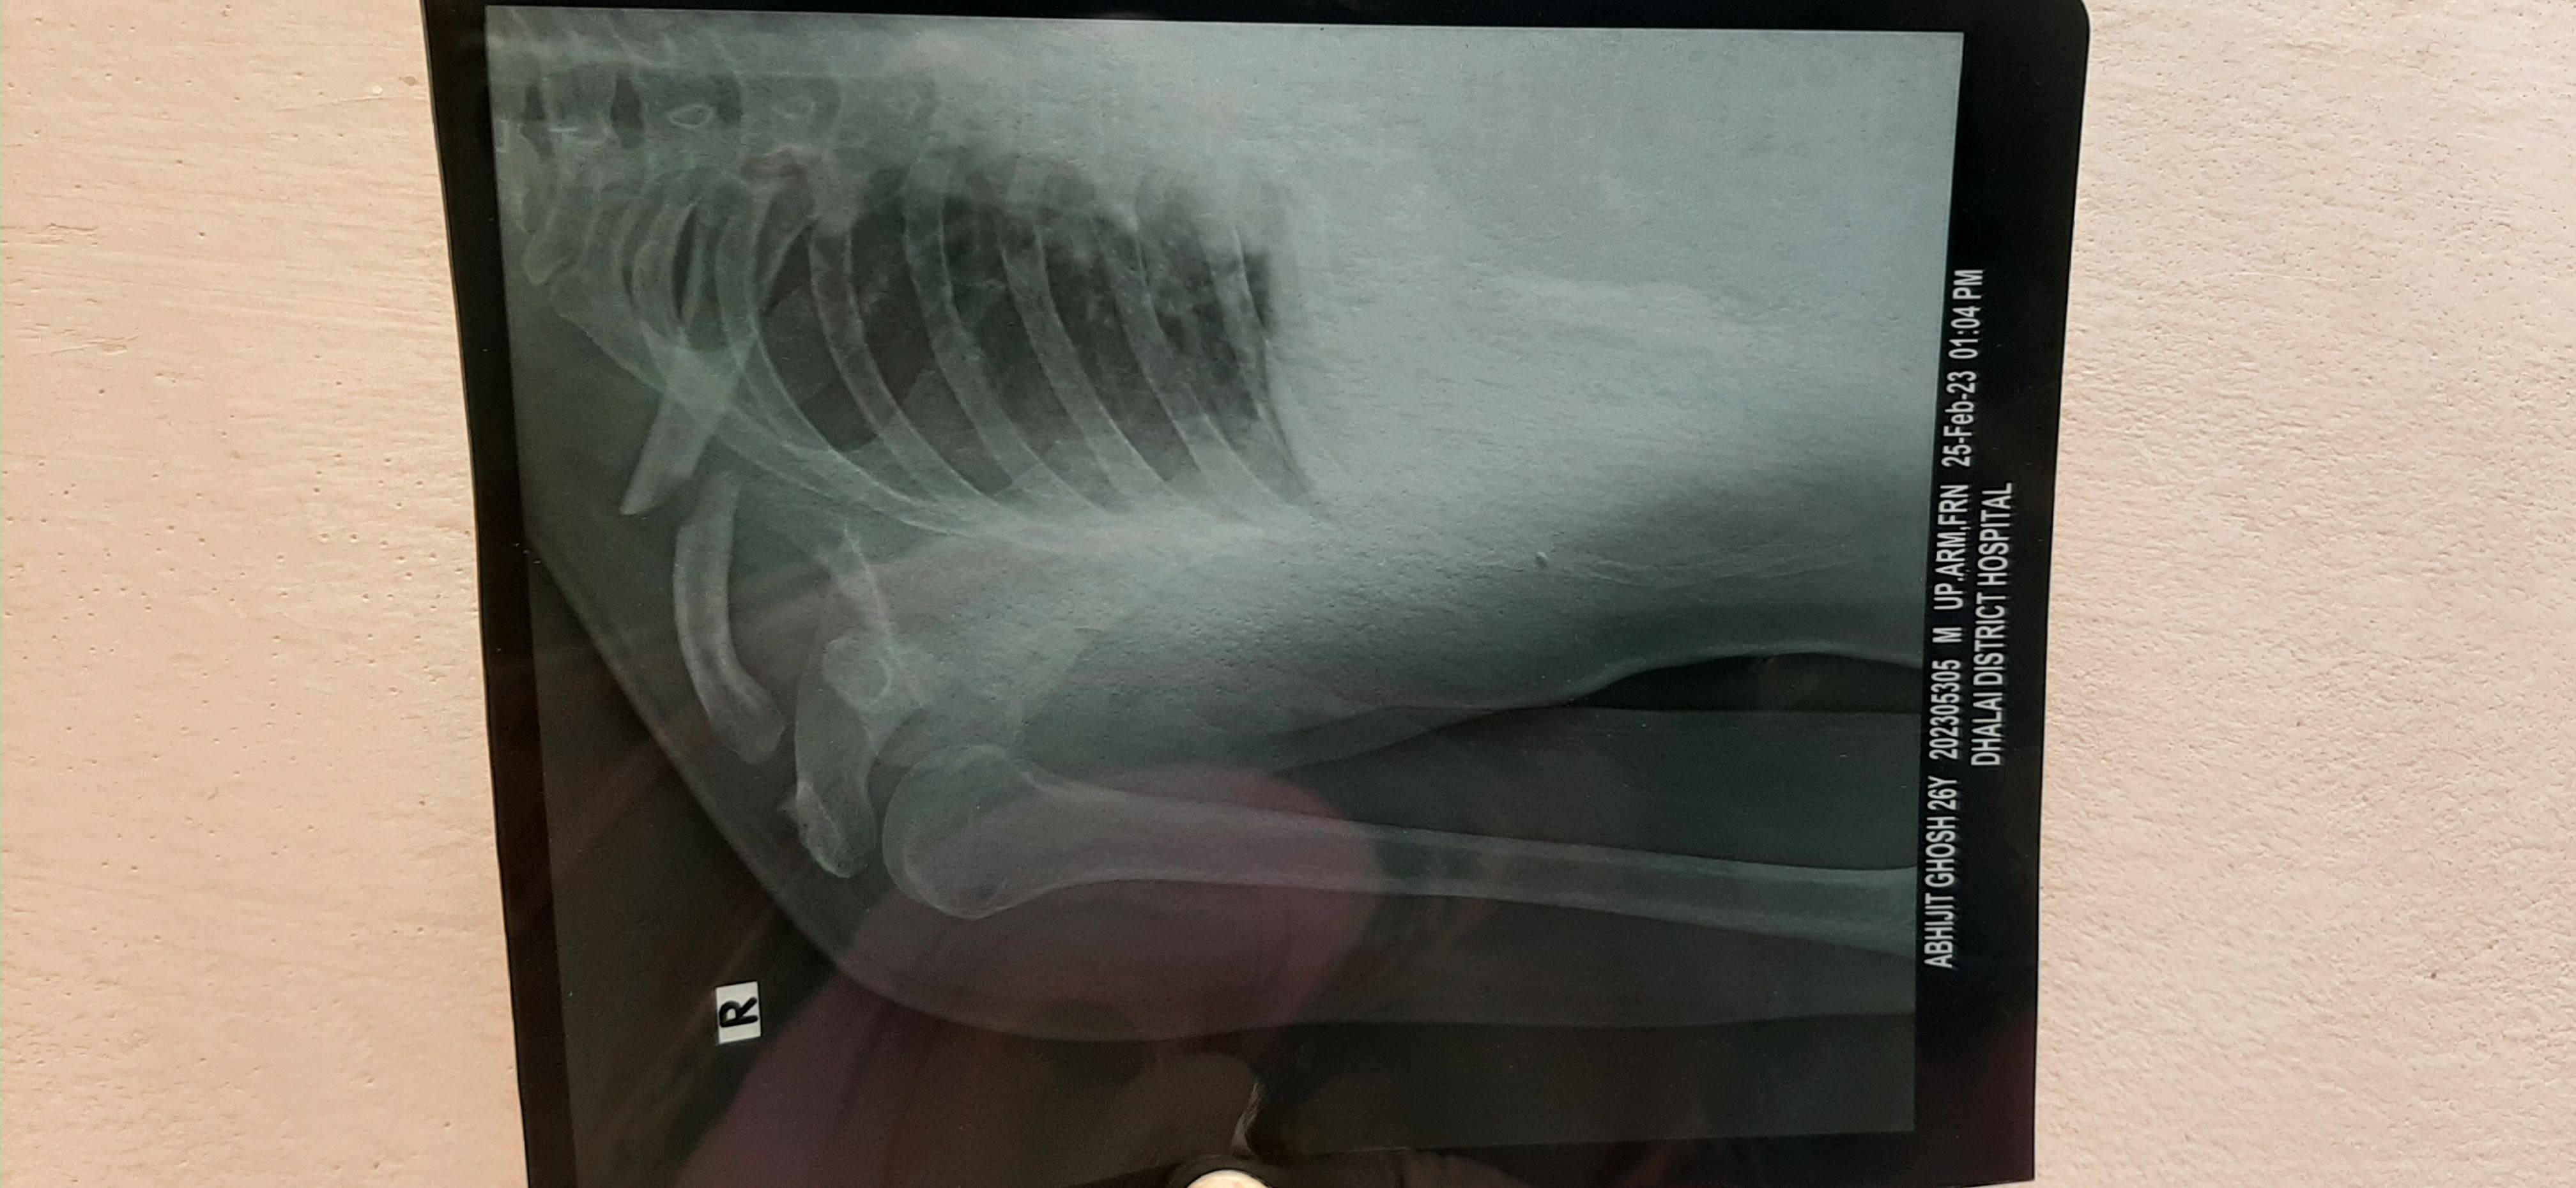

Abhijit Ghosh

- Wed 01 Mar 2023 03:54 am

In my fracture surgery is necessary or not?

Sir in a accident I have a fracture in my college bone. This is my X ray